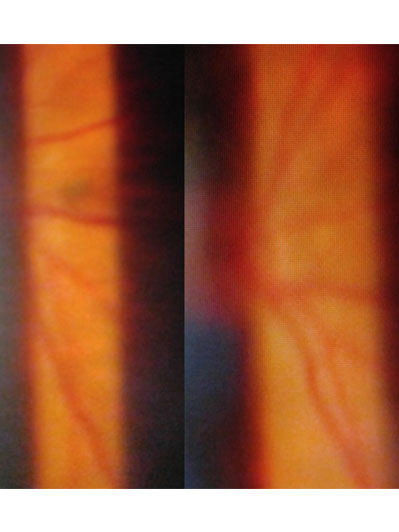

年屆四十至五十歲的病人,出現急症飛蚊大多是由於玻璃體液化以至出現「後玻璃體脫落」,當玻璃體從視神經盤脫離時,往往便出現較大和明顯的玻璃體「殘留物」,而導致嚴重飛蚊症狀,小部份病人亦會出現視網膜裂痕,出血和脫落等併發症,以致危害視力。雖然大部份病人沒有視力嚴重受損的風險,但較嚴重的飛蚊症狀會帶來視覺上的不便。治療此類飛蚊症,一般藥物治療效果有限,而侵入性外科手術 (玻璃體切除) 亦只適合如玻璃體出現嚴重出血或撕裂等併發症患者。

隨著激光技術的發展,近年已發展出激光治療飛蚊症,用於把較大和集中的玻璃體浮游物打散,以達到改善和消除飛蚊症狀,過程約十五至二十分鐘,沒有痛楚,並可於局部麻醉下進行。但並不是所有患有飛蚊症的人均適合做激光治療,如「飛蚊」物質較鬆散或位置太接近黃斑或晶體,便不適合進行此類激光治療,以免導致白內障或黃斑受損等併發症。